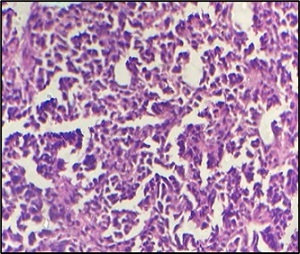

while 18F-FDG PET-CT showed a metabolically active nasopharyngeal lesion with FDG-avid (SUVmax~13.8) lymph nodes above and below the diaphragm, consistent with stage III disease and helped to exclude benign adenoid enlargement. The mass was excised surgically and sent for histopathology. Histopathology revealed diffuse infiltration by sheets of atypical medium- to large-sized lymphoid cells (Figure 2) displaying irregular round nuclei displaying moderate pleomorphism, vesicular chromatin, central prominent nucleoli and scant cytoplasm.

Figure 2. Microphotograph Displaying Fibrocollagenous Tissue Diffusely Infiltrating by Monomorphic Atypical Lymphoid Cell (100x; H and E).

Frequent atypical mitotic figures and large area of necrosis also seen (Figure 3).

Figure 3. Microphotograph Displaying Sheets of Medium to Large Sized Atypical Lymphoid Cells Displaying Vesicular Chromatin and Central Prominent Nucleoli. Numerous atypical mitotic figures are also seen. (400x; H and E).